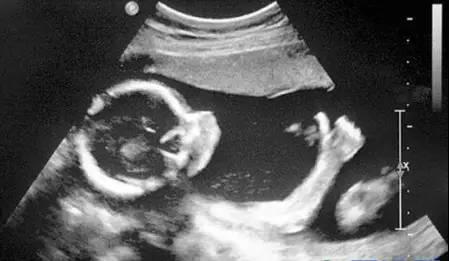

【B模式】--亮度模式B超也是目前最常用的超声检查方式,它将不同强度的回声信号,转换成不同的灰度,形成二维断层图像,医生和患者都能清晰看到器官的形态、大小和内部结构。

B超广泛应用于腹部超声检查,比如肝胆脾肾胰,妇产科检查,尤其是孕期评估,心脏超声,以及乳腺、甲状腺等浅表器官检查,这也是医院超声检查中最基础、最重要的模式。